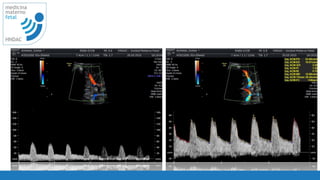

tecnica

• corte axial: talamos y base dek esfenoides

• visualizar el vaso y tomar la muestra lo mas

cercano a la carótida interna

• tomar 3 - 10 ondas

• lograr lo posible un angulo cercano a 0